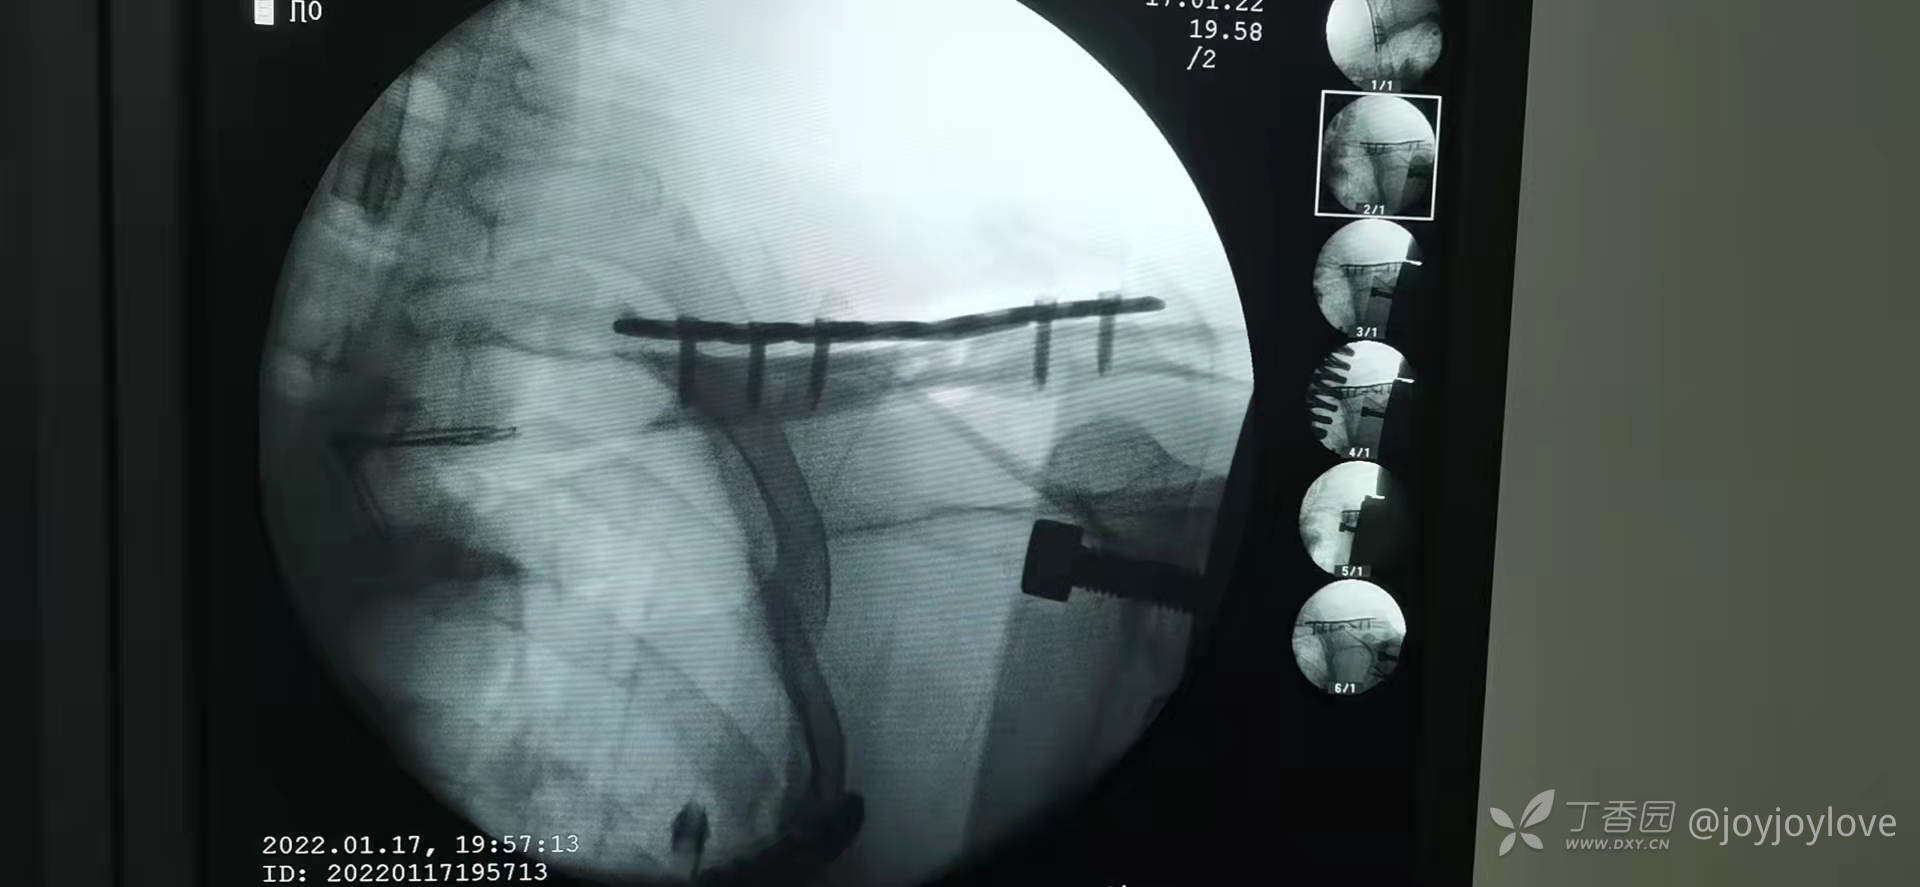

病例备忘录:2022锁骨

3.中段蝶形骨块,长斜块,3块骨折线,企图一枚拉力螺钉,结果拉力螺钉顶着皮质进,把骨折线顶开了,换成2枚拉力螺钉固定。

经验:

1.手术切口,铺单完毕后,触摸骨擦感,局部切开,暴露骨折端后再适度延长。

2.铺洞巾后,头颈部不撑起来,因为患者合并其他肋骨骨折,是全麻,不影响呼吸,所以不撑死洞巾,以免影响钻的应用

3.钻的时候满转慢推,后方垫骨膜起子,防止穿透软组织,损伤血管等软组织